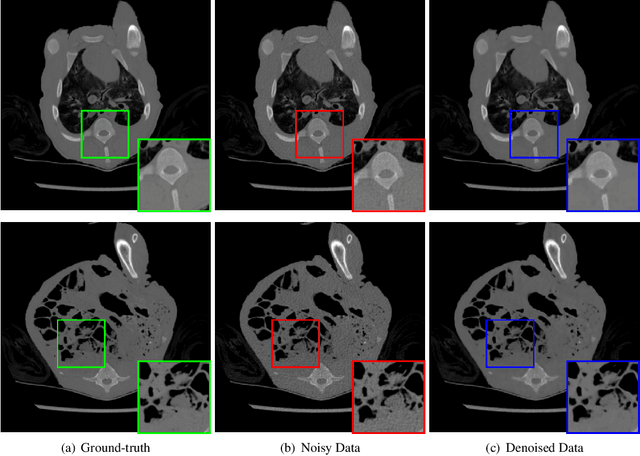

We study the problem of learning-based denoising where the training set contains just a handful of clean and noisy samples. A solution to mitigate the small training set issue is to train a denoising model with pairs of clean and synthesized noisy signals, produced from empirical noise priors; and finally only fine-tune on the available small training set. While transfer learning suits well to this pipeline, it does not generalize with the limited amount of training data. In this work, we propose a new training approach, based on meta-learning, for few-shot learning-based denoising problems. Our model is meta-trained using known synthetic noise models, and then fine-tuned with the small training set, with the real noise, as a few-shot learning task. Learning from synthetic data during meta-training gives us the ability to generate an infinite number of training data. Our approach is empirically shown to produce more accurate denoising results than supervised learning and transfer learning in three denoising evaluations for images and 1-D signals. Interestingly, our study provides strong indications that meta-learning has the potential to become the main learning algorithm for the denoising.